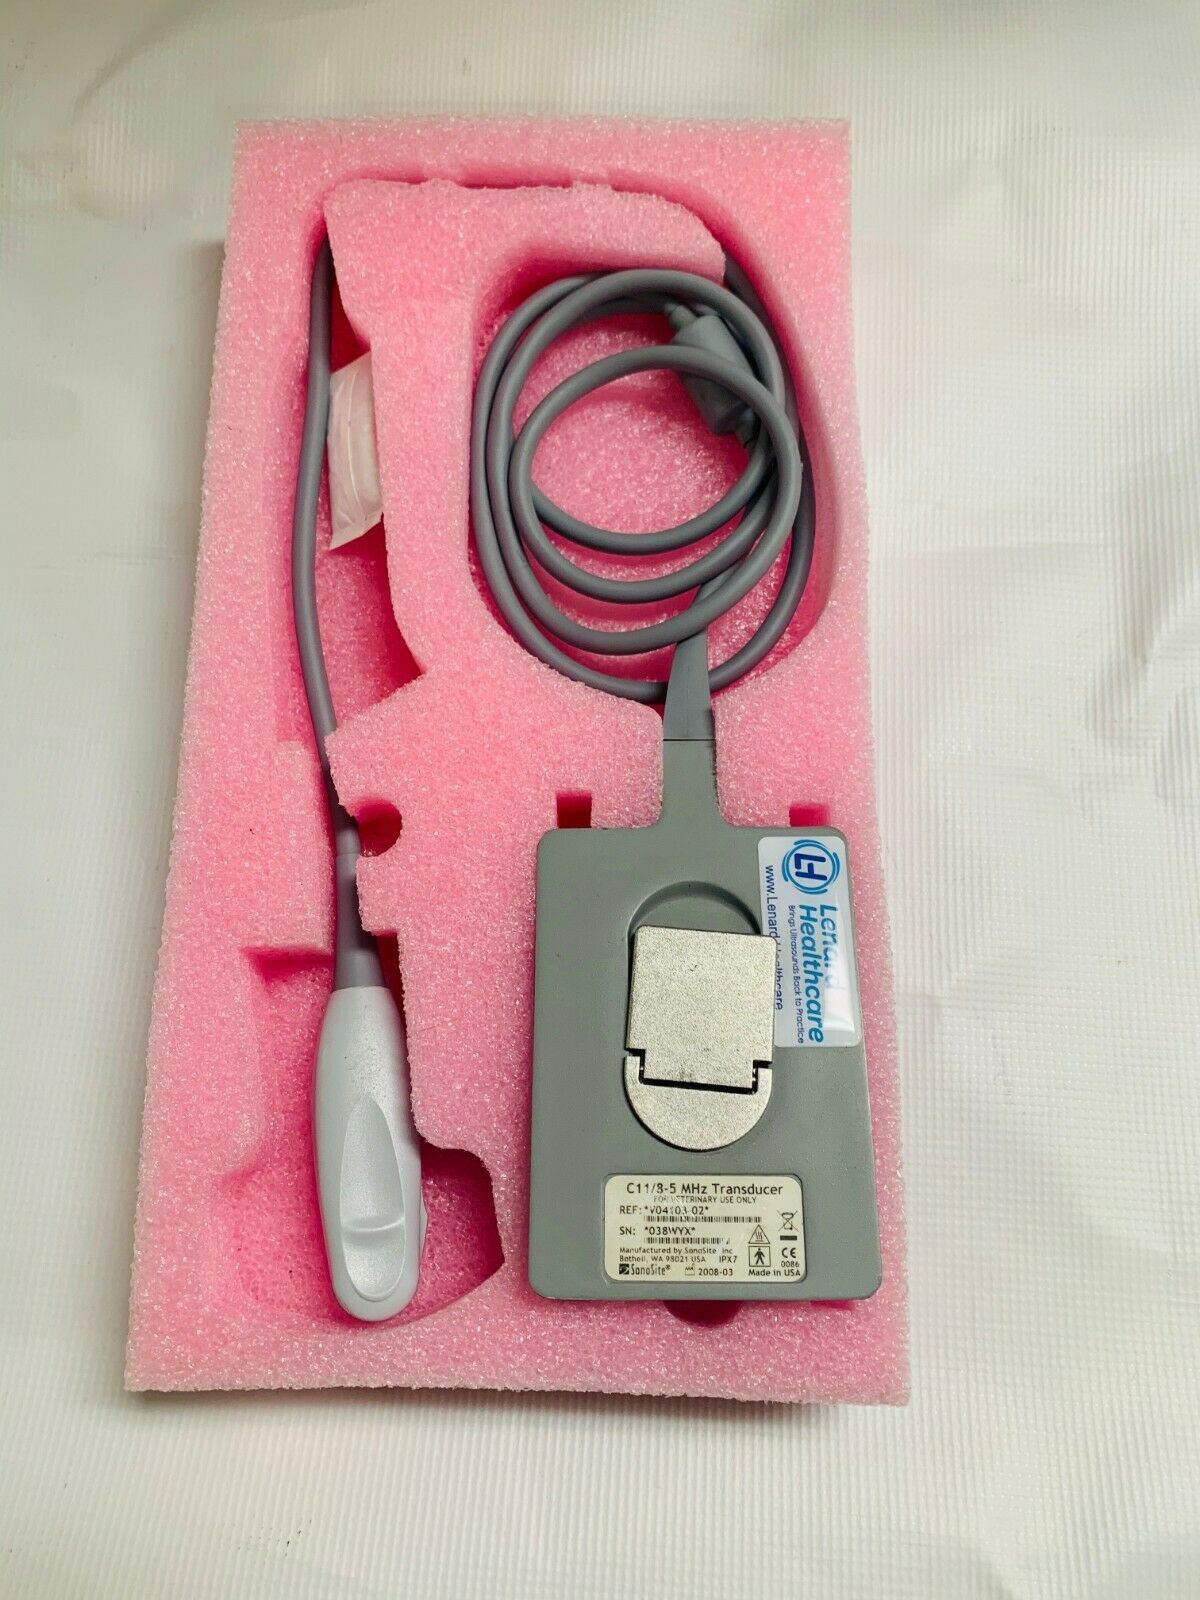

Veterinary Micro convex probe C11 8-5Mhz For Sonosite portable ultrasounds 2008

Sale price$ 1,639.18

Regular price$ 1,999.00